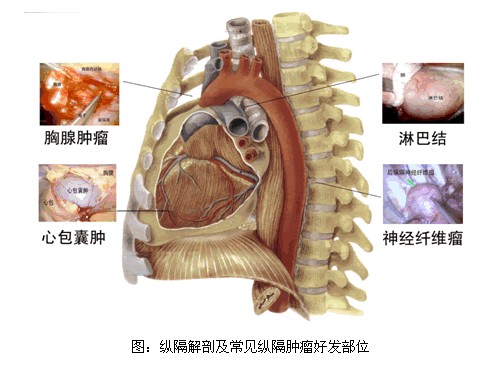

详解纵隔肿瘤以及鉴别诊断

图片尺寸783x625